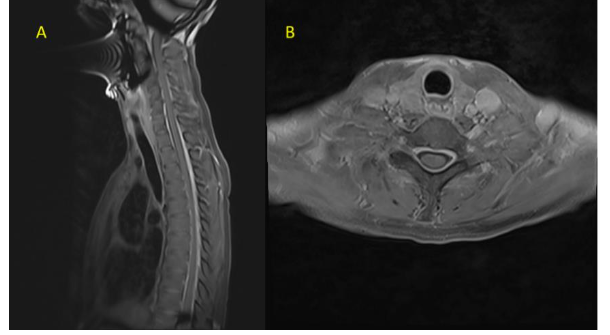

Her routine blood investigations including blood counts, liver and renal function tests were normal. Serum vitamin D and vitamin B12 levels were normal. CT brain and CT cerebral angiography was done in emergency to rule out any pituitary apoplexy, subarachnoid hemorrhage, vascular aneurysm, or vascular malformation, which was normal. Gadolinium-enhanced magnetic resonance imaging (MRI) showed bilateral subdural effusion, with diffuse smooth pachymeningeal enhancement (Figure 1). There was drooping of splenium of corpus callsosum, sagging of the midbrain, reduced mammillo-pontine distance, and pituitary hyperaemia. MRI of the spine showed smooth dural enhancement of the cervical and thoracic region. No CSF leak was noted in the contrast images. MR venogram showed engorgement of the venous sinuses. The imaging findings were in countenance with SIH (Figure 2). Ultrasound of the thyroid showed mild diffuse thyroid enlargement, with mild increase in vascularity.

Figure 1A-MRI T2 Axial image showing bilateral subdural effusion, Figure 1 B and 1C-post contrast T2 FLAIR and post contrast T1 weighted images showing diffuse smooth pachy meningeal enhancement